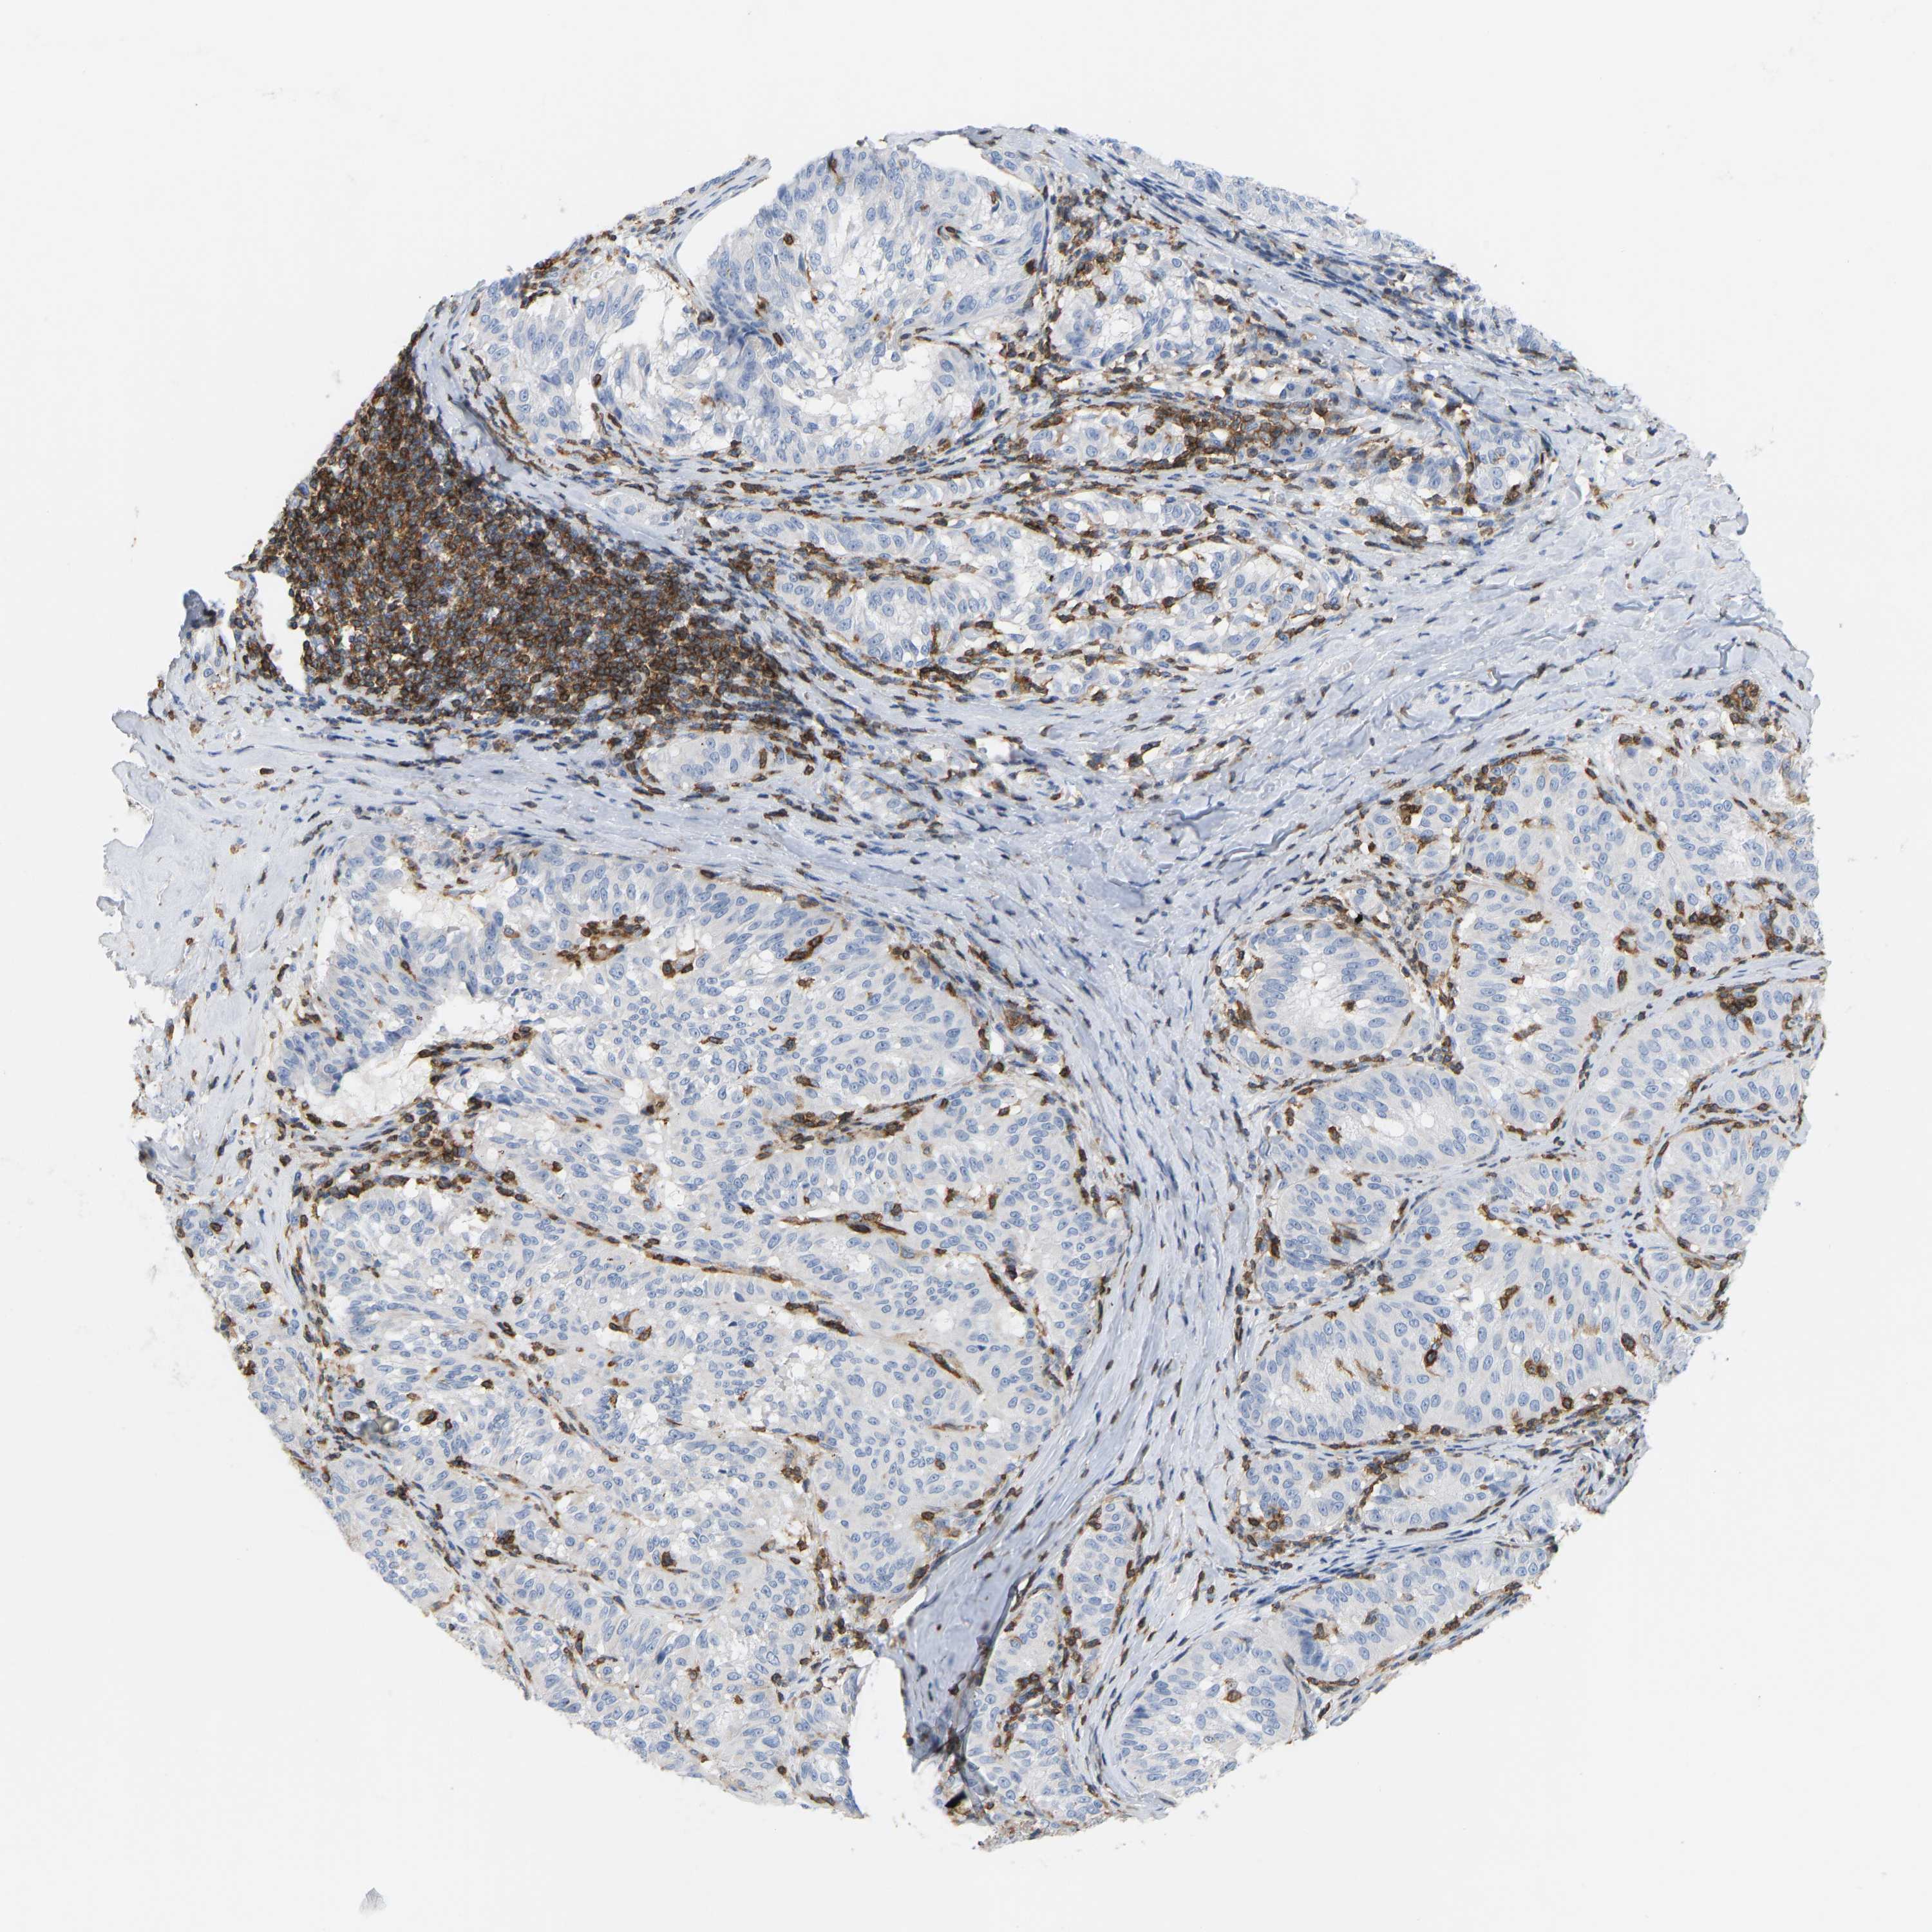

MELANOMA - Protein expressioni

A mouse-over function shows sample information and annotation data. Click on an image to view it in a full screen mode. Samples can be filtered based on level of antibody staining by selecting one or several of the following categories: high, medium, low and not detected. The assay and annotation is described here.

Note that samples used for immunohistochemistry by the Human Protein Atlas do not correspond to samples in the TCGA dataset.

Antibody stainingi

Antibody staining in the annotated cell types in the current human tissue is reported as not detected, low, medium, or high, based on conventional immunohistochemistry profiling in selected tissues. This score is based on the combination of the staining intensity and fraction of stained cells.

Each image is clickable and will lead to virtual microscopy that enables deeper exploration of all samples and also displays staining intensity scores, fraction scores and subcellular localization as well as patient and tissue information for each sample.

Antibody HPA018849

Antibody HPA019536

Antibody CAB033987

Staining

High

Medium

Low

Not detected

Intensity

Strong

Moderate

Weak

Negative

Quantity

>75%

75%-25%

<25%

None

Location

Nuclear

Cytoplasmic/membranous

Cytoplasmic/membranous,nuclear

Malignant melanoma, NOS

Malignant melanoma, Metastatic site